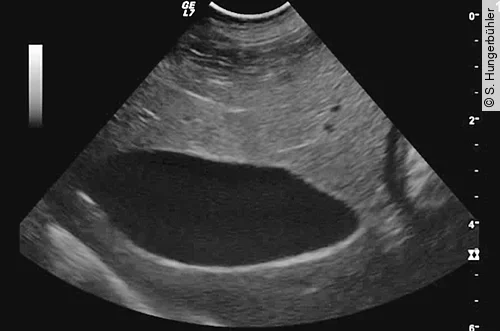

Bei der Sonografie liegt die GB rechts der Medianen und ist in der Regel mittels subkostaler Anschallung gut erreichbar. Im sonografischen Normalbefund stellt sich die GB in der Längsachse als birnenförmige und im Querschnitt als runde anechogene dünnwandige Struktur dar (Abb. 1). Bei tiefbrüstigen Patienten, kleiner Leber und hochdorsaler Lage der GB bedarf es vereinzelt der transinterkostalen Anlotung. Aufgrund der geringen Auflagefläche und des Frequenzspektrums im Bereich um 8–12 MHz sind daher Mikrokonvexsonden besonders für die Untersuchung geeignet.